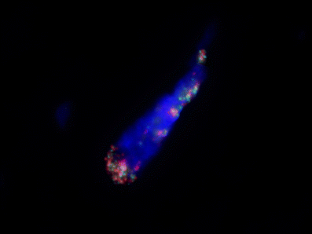

Fig. 1

Fig. 2

Fig. 3

Fig. 4

Fig. 5

Fig. 6

Fig. 7

Fig. 8

Fig. 9

Fig. 10

Fig. 11

Fig. 12

Fig. 13

Fig. 14

Fig. 15

Fig. 16

Fig. 17